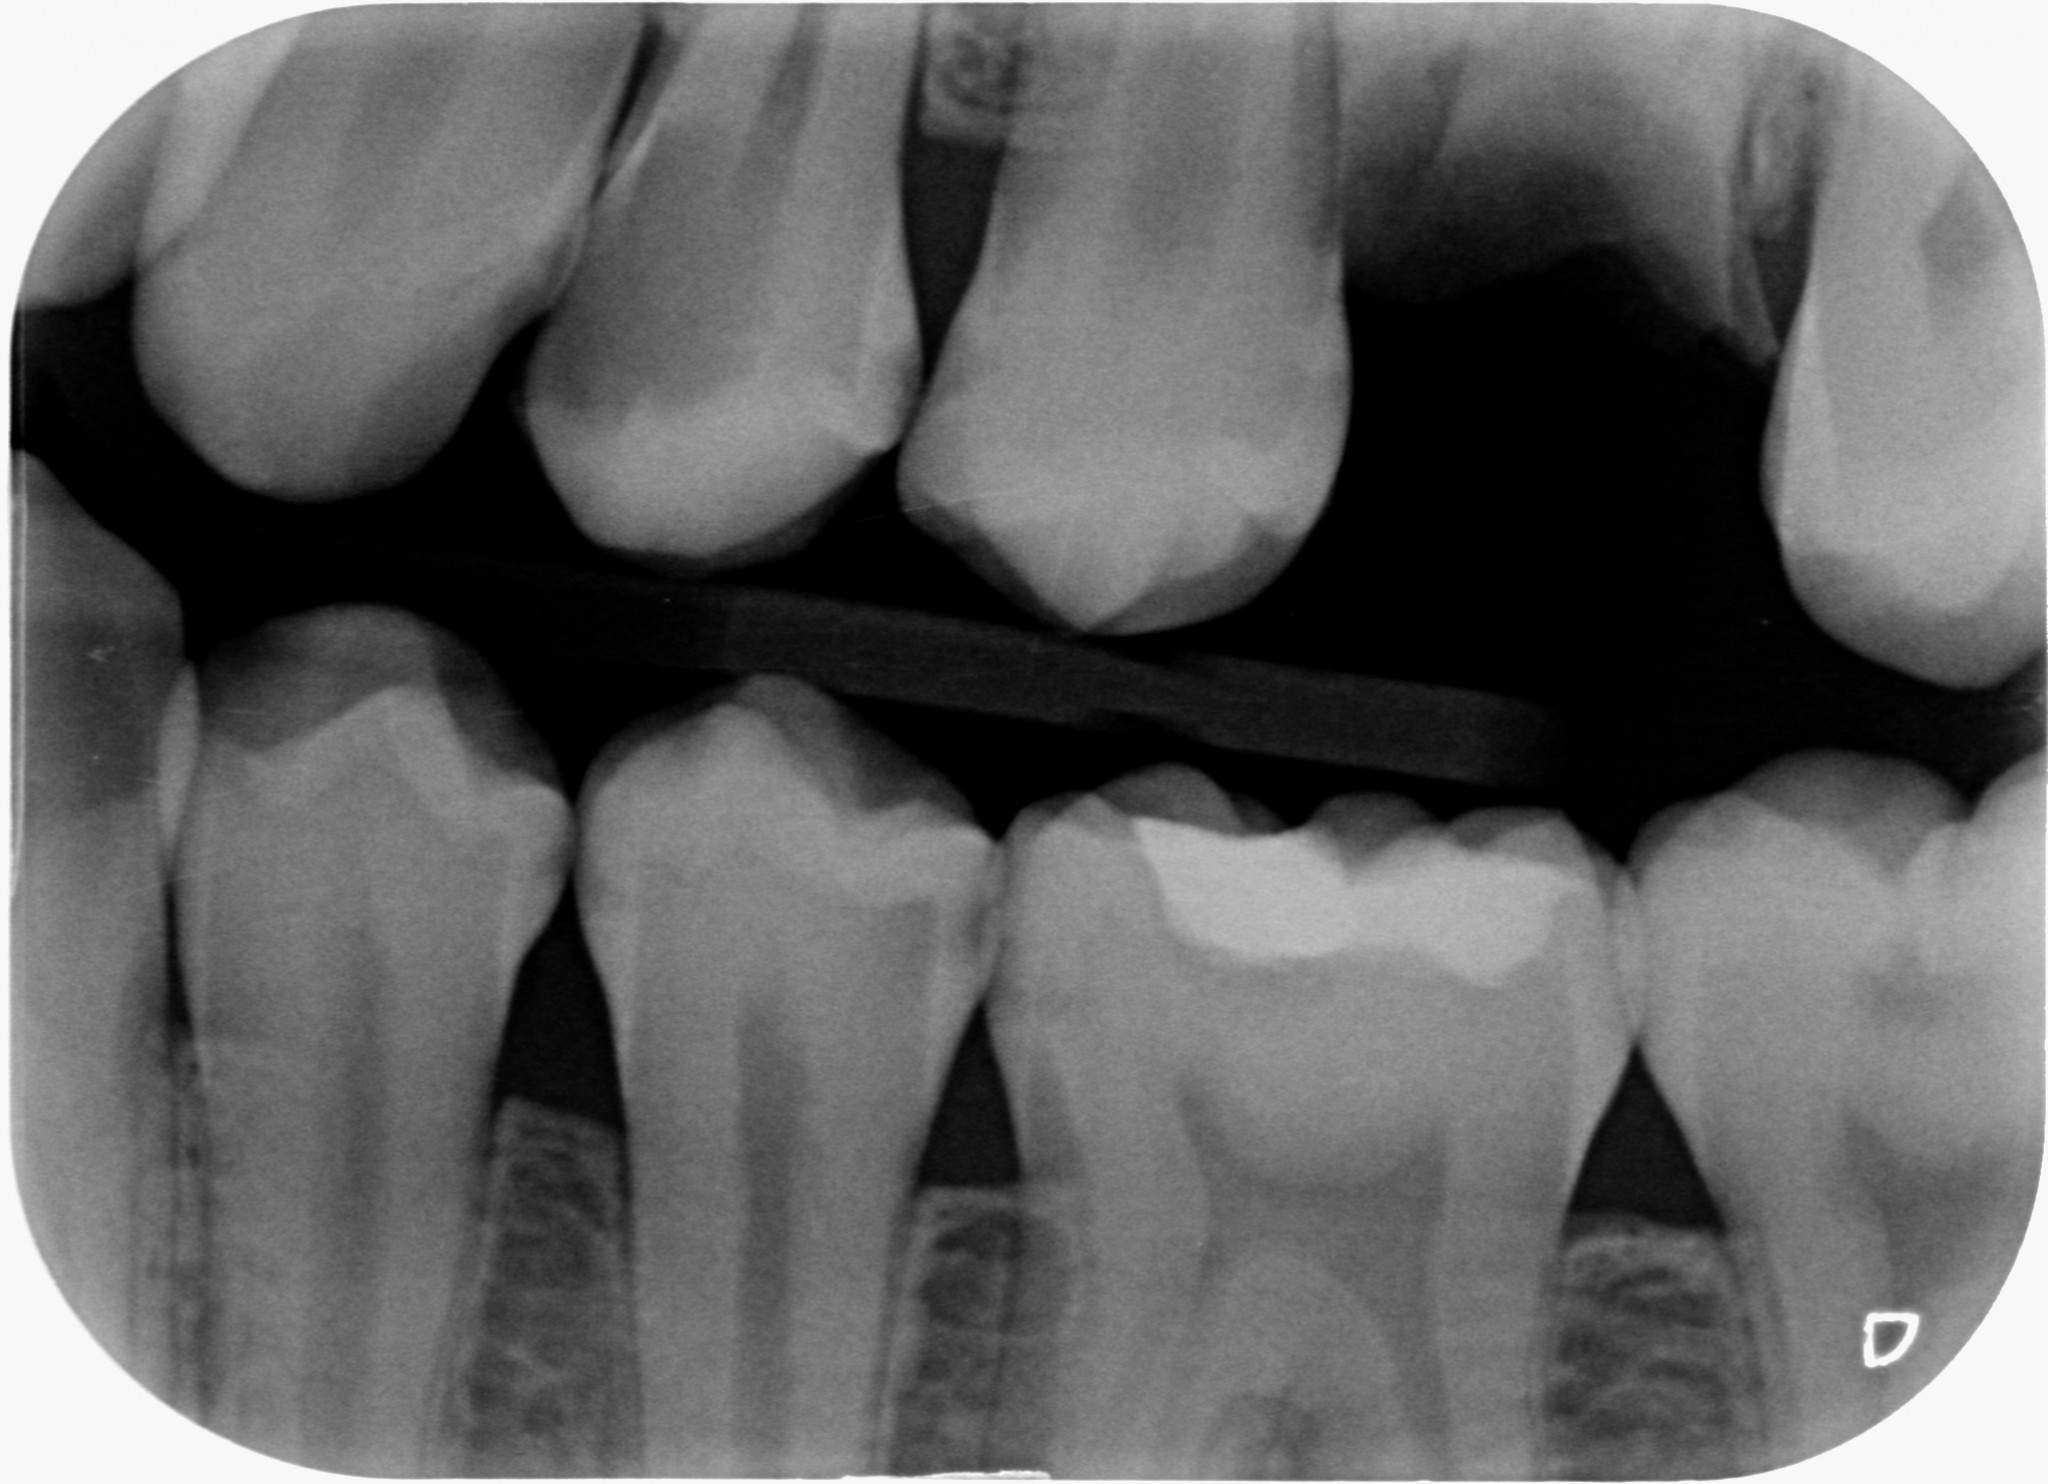

Se invadere l’ampiezza biologica massacra l’osso e genera tasche spiegami perchè in queste due rx scattate a 4 anni di distanza tra loro, l’osso distale al 4.7 mesializzato, che sarà da estrarre per altri motivi, sia sempre uguale, con un risentimento legato alla carie primaria che c’era stata verosimilmente decenni prima…?

Il tutto con una amalgama ben più difficile da rifinire rispetto alla superficie di un composito flow!

Come puoi vedere dalle immagini qui sotto, il caso che ho mostrato nella rx precedente a 4 anni di distanza mostra che nè l’osso nè la papilla risentono di questo terribile insulto…